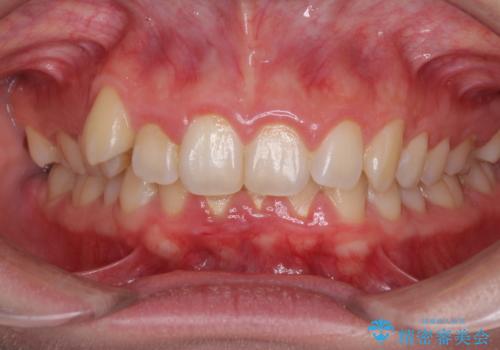

「整形した?」と言われるほどの変化! 口元を矯正治療で改善 鼻を高くしたわけでも、アゴに何か入れたわけでもありません。